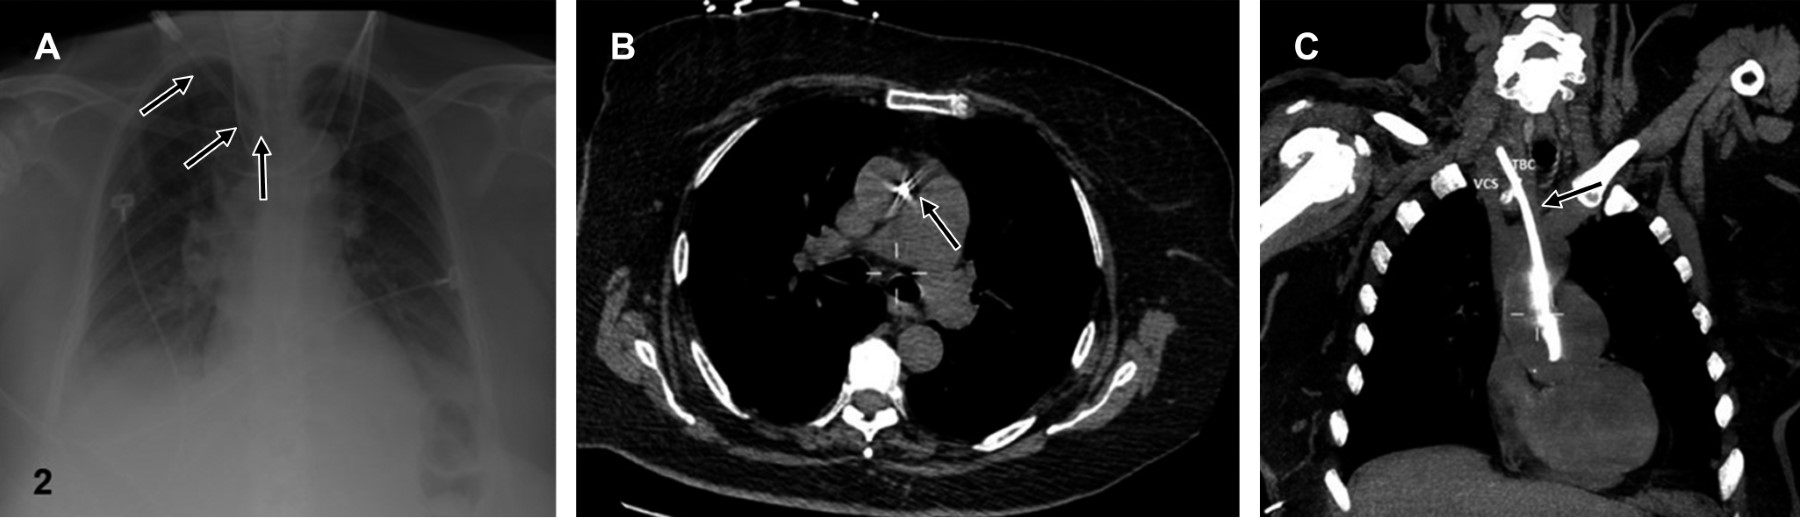

Evaluación radiológica: la evaluación del cateterismo como exitoso, ya sea de acceso yugular o subclavio, debe basarse en el conocimiento de los marcadores anatómicos en la radiografía.3 La identificación inicial del catéter es crucial, y deben tomarse en cuenta los siguientes puntos; el extremo distal del catéter debe localizarse distal a la última válvula venosa que corresponde a la confluencia de ambas venas braquiocefálicas formando la vena cava superior (VCS), que en la placa de tórax se proyecta en el borde interno de la primera costilla y lateral al borde esternal derecho (es valioso comprender que la VCS presenta una estrecha relación con los vasos supraaórticos a este nivel, ya que se localiza anterior a éstos).7,9,18

El trayecto de VCS nos ofrece otras referencias anatómicas, ya que sigue un curso perpendicular y ulterior al segundo y tercer espacio intercostal (línea paratraqueal derecha), alcanzando la unión cavoatrial (Figura 3) antes de ingresar al pericardio (borde superior del tercer cartílago costal derecho), y posteriormente ingresar al saco pericárdico.9 En la radiografía, Baskin KM y colaboradores proponen situar la unión cavoatrial dos cuerpos vertebrales por debajo de la carina. Diversos autores recomiendan que todas las puntas de catéter deben situarse por encima de la carina.9,20

Al revisar la literatura, es notable la falta de consenso en cuanto a las referencias anatómicas, como es el caso de la unión cavoatrial, en el que Chan TY y colaboradores reportan discrepancia interobservador al identificar dicha estructura en hasta 4.3 cm.21